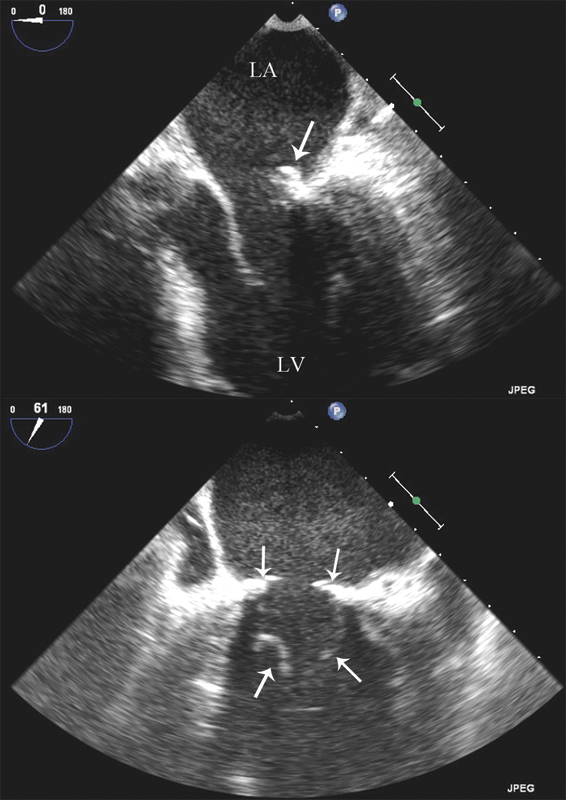

فحوصات تشخيصية لبعض امراض القلب والشرايين التاجية